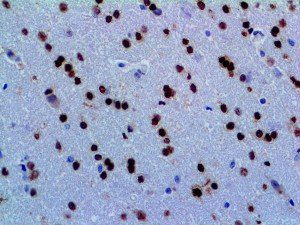

The first cytokines released are interleukin 1β (IL-1β) and tumor necrosis factor-α (TNF-α), which attract a variety of circulating white blood cells (WBCs) to the infection site, including neutrophils, monocytes, macrophages, and natural killer (NK) cells. This response, along with the antipathogenic chemicals released by these cells (i.e., complement), comprise the innate immune response. These cells directly attack the invading pathogen and also release additional cytokines, chief among them interleukin-1 and 6 (IL-6). IL-6 is essential for invoking the adaptive immune response, which calls T-cells, B-cells, and T helper (Th) cells to the infection site. IL-6 also stimulates further recruitment, proliferation and activation of macrophages.

It is the ICU physician who is most likely to witness one of the deadliest manifestations of the abnormal immunological response, the cytokine storm syndrome (CSS). This response is also referred to by some as the cytokine release syndrome (CRS). CSS is characterized by continuous activation and expansion of macrophage and lymphocyte populations, which secrete large amounts of cytokines, causing the cytokine storm. This massive cytokine release is akin to hemophagocytic lymphohistiocytosis (HLH) disease, a syndrome characterized by initial unchecked and persistent activation of cytotoxic T lymphocytes and NK cells.